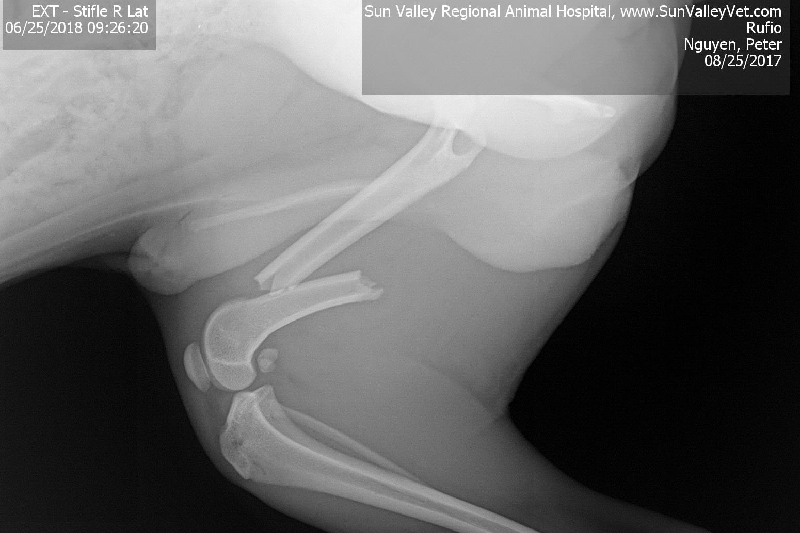

My name is Phero Peter and this is Rufio. We had a bad accident. We are still finishing up our move and Rufio had jumped onto our highest furniture and down onto my luggage that he slipped off of and broke his leg.

The money is for Rufio's orthopedic surgery. The Sun Valley Animal Hospital had attempted to do a "splint surgery" for Rufio and failed. They still gave me the bill for it but removed the cost of the attempt.

The vet said the cost will be between 2905.60 to 3641.95 so anything helps.